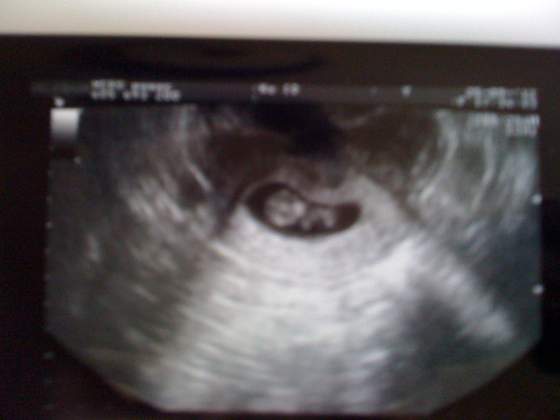

No to jestem po wizycie,

chyba jest dobrze - tak przynajmniej twierdzi Pani doktor. Fasola nie widać ponoć jeszcze, za to widać większy domek dzidziola (odpowiadający 4w5d-ponoć takie odchyłki są w normie) no i jego lodówkę czyli pęcherzyk żółtkowy. Pani dr stwierdziła że na razie wszystko ok, a na serduszko mam sobie spokojnie dać 2 tygodnie...

a to fota:

Zobacz załącznik 502262Zobacz załącznik 502263

szczerze gdyby nie lekarz pomyslalabym że to fasolka, ale tymczasem to ponoć pęcherzyk żółtkowy czyli to z czego fasolka na samym początku czerpie substancje odżywcze:)

tak więc póki co jest dom i lodówka, lokator się ukrywa...